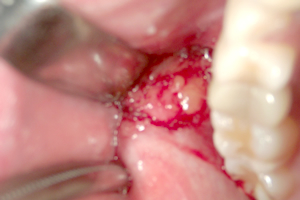

写真で見る「バッカルファットを除去する様子」

① 粘膜切開

② 粘膜剥離